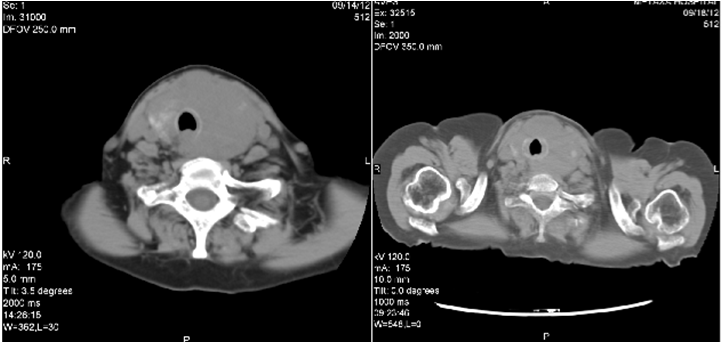

Evaluation for systemic disease with thorax, abdomen and pelvis imaging and bone marrow aspiration excluded other neoplastic foci. According to the Ann Arbor guidelines for primary thyroid lymphoma the patient had stage IIE disease at diagnosis (involvement of the thyroid and lymph nodes on the same side of the diaphragm). After surgery the patient underwent systemic chemotherapy with the R-CNOP chemotherapeutic protocol, i.e. rituximab (anti CD-20 antibody) 580mg, mitoxandrone 15 mg, cyclophosphamide 1160 mg, vincristine 2mg and methylprednisolone 16mg cumulative dose. Radiation therapy was planned after the chemotherapy cycles. The post-chemotherapy CT scan showed a marked regression of the mass with decompression of the trachea (Figure 3).

Figure 3 Neck CT-scan after chemotherapy.